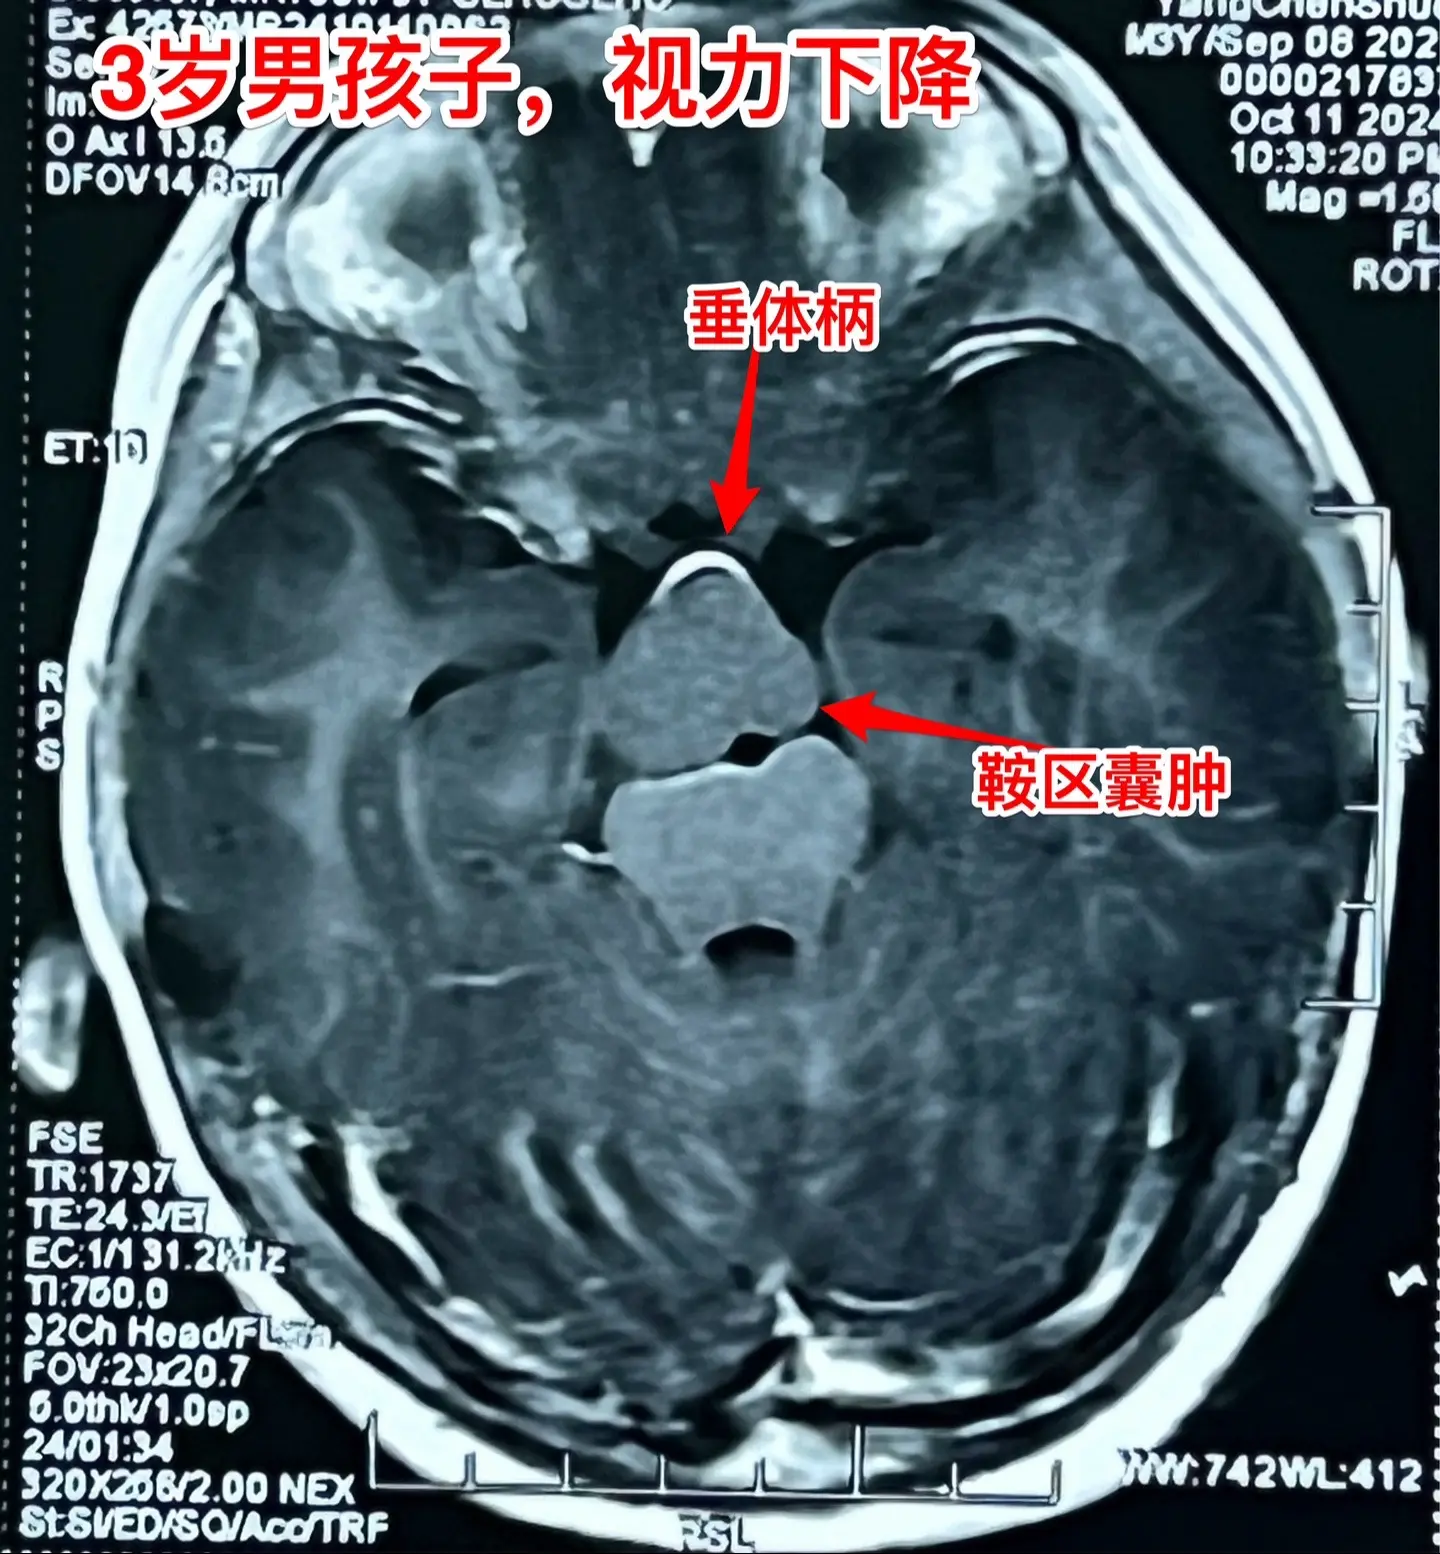

鞍区高密度囊肿-高密度不等于钙化。拉克氏囊肿在CT扫描中大多数呈低密度影,少数呈现比较均匀的高密度影,但是绝对不是钙化。不能误认为是颅咽管瘤。 三岁男孩子因偶然原因行CT扫描发现鞍区病变。测视力才发现患儿的视力有下降(0.3)。根据CT、磁共振可以判断这是拉克氏囊肿,病变没有钙化。 拉克氏囊肿如果压迫视神经、视交叉造成视力下降或者视野缺损,则有手术指征。 今日10.25经翼点入路将病变切除。术中快速冰冻报告为拉克氏囊肿。